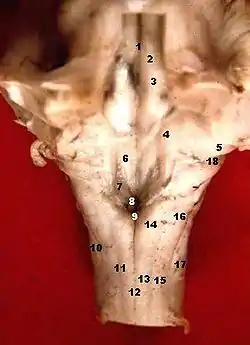

![]() Human caudal brainstem posterior view (Colliculus facialis is #3) | |

The facial colliculus is an elevated area located in the pontine tegmentum (dorsal pons), within the floor of the fourth ventricle (i.e. the rhomboid fossa). It is formed by fibres from the facial motor nucleus looping over the abducens nucleus. The facial colliculus is an essential landmark of the rhomboid fossa.[1]

The facial colliculus occurs within the rhomboid fossa (i.e. the floor of the fourth ventricle) where it is placed lateral to its (midline) median sulcus.[1]